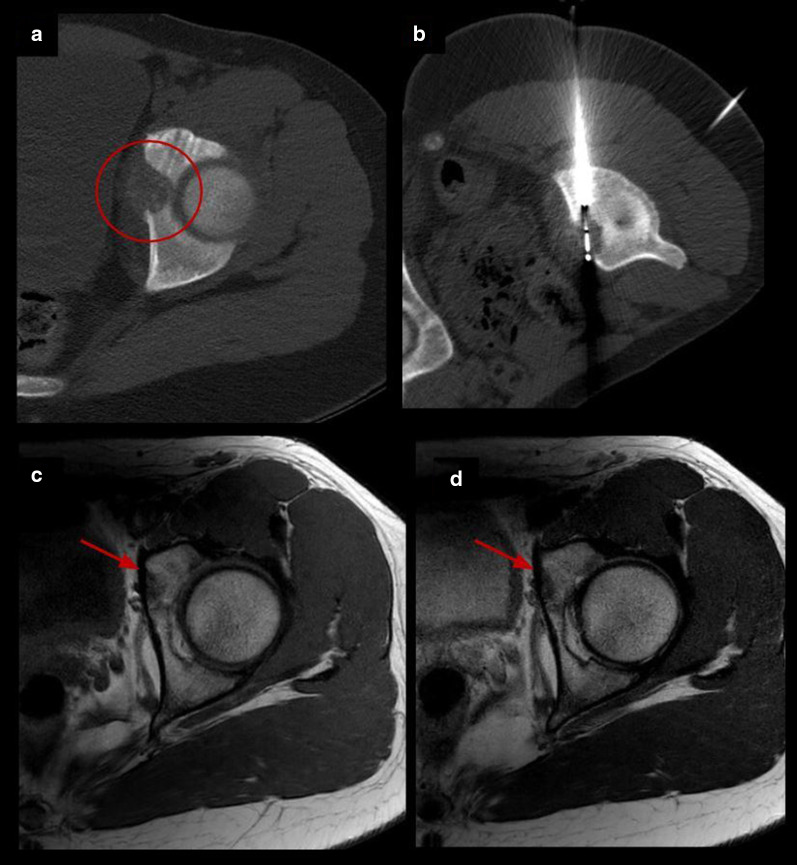

Fig. 5.

Acetabulum osteoblastoma cryoablation. a Axial CT images demonstrating an expansive osteolytic tumor with partial matrix mineralization in the left acetabulum corresponding to osteoblastoma (circle). b Axial CT exhibiting one cryoprobe placed within the nidus. c, d Follow-up MRI images 15 months after treatment with complete resolution of the lesion (arrows)